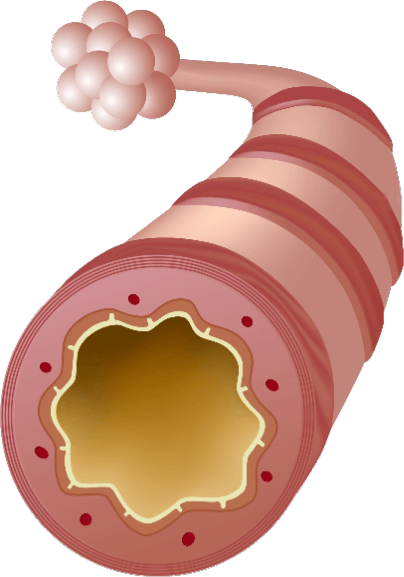

MÉCANISME D’ACTION (MOA)

EA 575MD est également unique pour aider à améliorer les fonctions respiratoires chez les patients souffrant de bronchite.

- L'EA 575MD est un principe actif issu de la feuille de lierre naturelle qui liquéfie le mucus collant piégé dans les voies respiratoires des poumons.

- Il agit alors comme un expectorant, permettant au mucus d'être expulsé plus facilement.

- Lorsque les voies respiratoires se détendent et s'élargissent, le patient peut respirer mieux et plus confortablement.